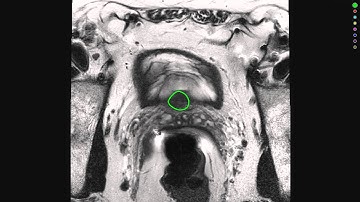

RadiologyPlatform - Automated segmentation of the prostate gland using AI-based algorithms